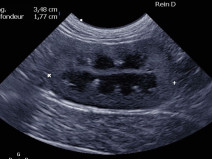

• Plan modulaire en échographie - Module avancé d'échographie abdominale

Principes du plan modulaire d’échographie :

Le plan de formation est composé d’un module de base d’échographie abdominale (2 jours), d’un module avancé en échographie abdominale pour être capable de reconnaitre les lésions abdominales les plus fréquemment rencontrées (2 jours). Pour celles et ceux qui souhaitent aller encore plus loin, nous proposons aussi 2 modules spécifiques, d’une...

Formation complète

Le plan de formation est composé d’un module de base d’échographie abdominale (2 jours), d’un module avancé en échographie abdominale pour être capable de reconnaitre les lésions abdominales les plus fréquemment rencontrées (2 jours). Pour ceux et celles qui souhaitent aller encore plus loin,...

Le plan de formation est composé d’un module de base d’échographie abdominale (2 jours), d’un module avancé en échographie abdominale pour être capable de reconnaitre les lésions abdominales les plus fréquemment rencontrées (2 jours). Pour ceux et celles qui souhaitent aller encore plus loin, nous proposons aussi 2 modules spécifiques, d’une...